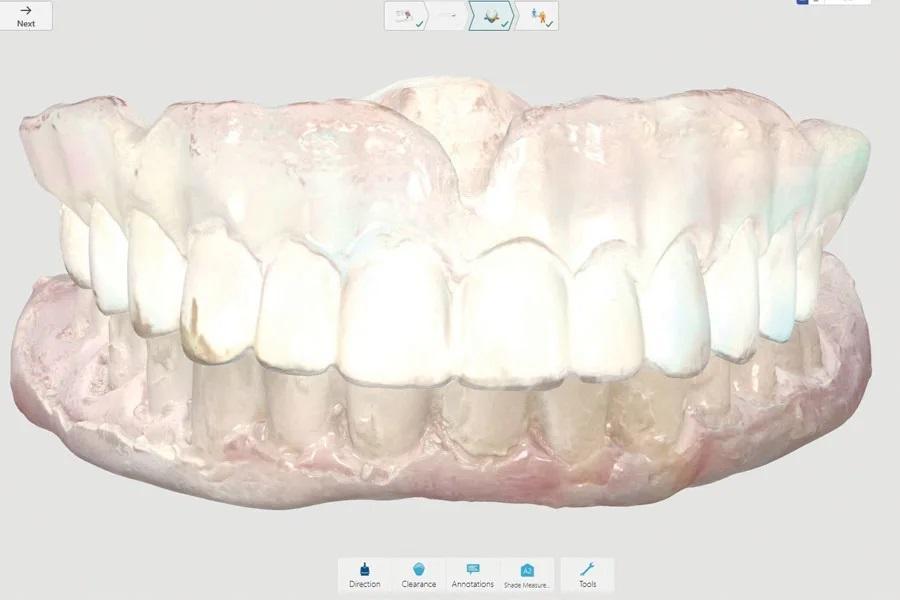

Были выполнены цифровые сканы верхней и нижней челюстей для мукостатического оттиска (Фото 10 и Фото 11). Основания зубных протезов с укороченными краями были изготовлены по напечатанным моделям и поставлялись с восковыми окклюзионными валиками. Окклюзионная высота, эстетика и фонетика были оценены традиционным образом, все эти аспекты были зафиксированы на восковых валиках. Была проведена традиционная примерка расположения зубов, и зубные протезы были установлены с материалом для функциональных оттисков. Через 1 неделю на кратковременные мягкие вкладыши обоих зубных протезов был нанесен жидкий пластификатор (тканевый кондиционер) (Hydro-Cast) для облегчения формования в соответствии с протоколом производителя (Фото 12). Еще через неделю с помощью сканера TRIOS было выполнено окончательное цифровое сканирование сформованных зубных протезов, скан был отправлен в электронном виде в лабораторию для дублирования. Конечно, в этом случае возможна передача зубных протезов для замены, но в этом нет необходимости, поскольку оригинальные зубные протезы, использованные при изготовлении, могут быть использованы повторно для получения миофункционального слепка в будущем, когда понадобятся новые зубные протезы.

Фото 10 и Фото 11. Клинический случай 2. Цифровые сканы верхней (Фото 10) и нижней (Фото 11) челюстей в аналоговом процессе для получения мукостатического оттиска.